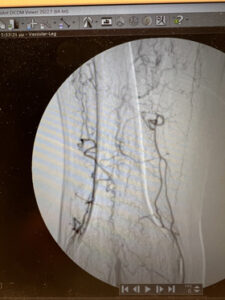

Ενδαγγειακή αποκατάσταση απόφραξης της ιγνυακής αρτηρίας

Ενδαγγειακή επαναγγείωση της ιγνυακής αρτηρίας

πλήρη ύφεση της συμπτωματολογίας

μετά απο 24 ώρες επιστροφή στην καθημερινότητα